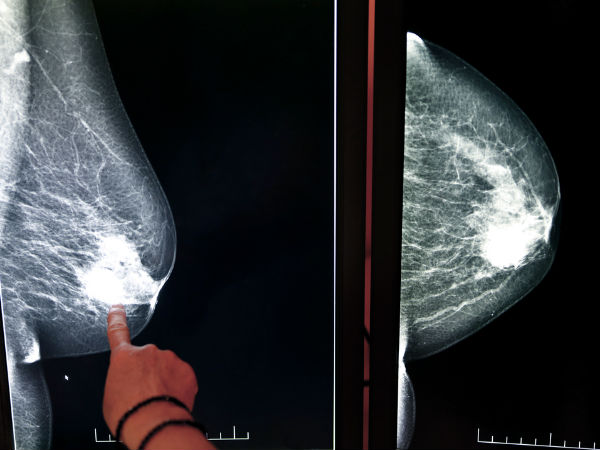

മാറിടങ്ങള് മസാജ് ചെയ്യുമ്പോള് കോശങ്ങളിലെ ലിംഫ് ഉല്പാദനം വര്ദ്ധിയ്ക്കുന്നു ഇത് അസുഖങ്ങള് തടായനുള്ള കോശങ്ങളുടെ ഉല്പാദനത്തെ സഹായിക്കും. ഇതുവഴി ബ്രെസ്റ്റ് ക്യാന്സര് പോലുള്ള പല രോഗങ്ങളും തടയാന് സഹായിക്കും.